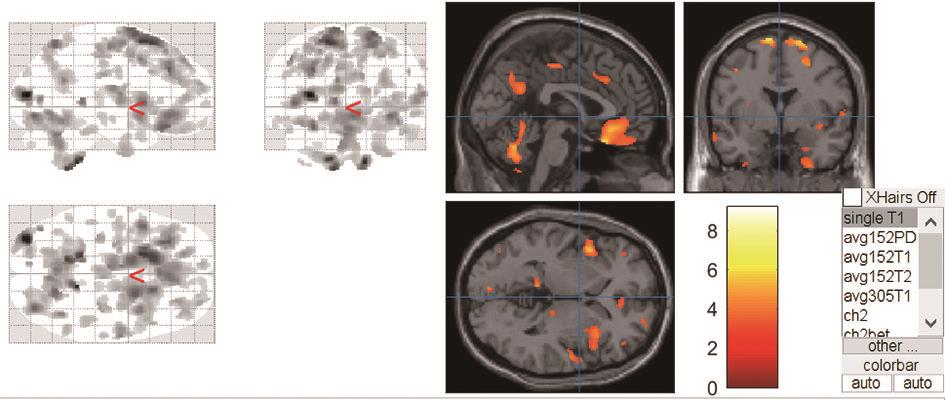

• 正常成人与伴吞咽障碍的急性脑梗死患者吞咽相关脑功能区激活机制的血氧水平依赖功能磁共振研究

摘要:目的 运用血氧水平依赖功能磁共振(blood oxygenation level dependent-functional magnetic resonance imaging,BOLD-fMRI)技术对伴吞咽功能障碍的急性脑梗死患者和正常成人在吞咽活动时相应的脑功能区域激活特点进行研究,探索急性脑梗死患者吞咽功能障碍恢复过程中相关的脑功能区域调控方式。方法 选取2018年7月至2021年7月在昆明医科大学附属延安医院住院的伴吞咽障碍的急性脑梗死患者150例和正常成人100例,对其进行BOLD-fMRI扫描,记录两者在吞咽活动时相关脑功能区域的激活体积和强度,并对比两者间的差异。结果 共收集病例组150例,其中右侧脑梗死组患者50例,男29例,女21例,平均年龄(56.22±7.33)岁;左侧脑梗死组患者100例,男61例,女39例,平均年龄(58.07±6.84)岁;对照组100例,男57例,女43例,平均年龄(53.56±11.41)岁。对照组吞咽活动时激活的相关脑功能区域特点显示:两侧初级运动皮层中枢(BA4区)、运动前区/辅助运动区(BA6/8区)、缘上回(BA40区)、岛叶(BA13区)、颞上回(BA22区)、扣带回皮层(BA24区)、额叶内侧面(BA32区)、延髓、脑桥、基底核团、丘脑、小脑及左侧颞极(BA38区)和右侧颞横回(BA41区)等脑功能区激活体积和强度增加,左侧BA4区、BA40区、小脑激活体积较右侧大,差异有统计学意义(P<0.05);左右两侧脑区的激活强度差异无统计学意义(P>0.05)。右侧脑梗死病例组患者BOLD-fMRI扫描各脑区激活体积显示:右侧BA4区、BA6/8区激活体积较对照组减小,左侧BA6/8区、BA4区激活体积较对照组增大,双侧后扣带回皮层的BA23和顶叶内侧面BA31区体积较对照组增大,左侧视觉中枢的BA18/19和BA41区皮层激活体积较对照组增大,差异有统计学意义。右侧BA4区、BA6/8区、BA40区、BA13区激活强度较对照组降低,差异有统计学意义。左侧脑梗死病例组患者BOLD-fMRI扫描各脑区激活体积显示:左侧BA4区、BA6/8区的激活体积较对照组减小,右侧BA4区、BA6/8区激活体积较对照组增大,双侧BA23/31区、左侧BA41区、双侧BA7区、双侧BA18/19区和双侧小脑激活体积较对照组增大,差异有统计学意义。左侧BA4区、BA6/8区、BA40区、BA13区激活强度较对照组降低,差异有统计学意义。结论 双侧运动、运动前、感觉、嗅觉、听觉、脑干、小脑、基底核团等脑功能区均参与调控正常人的吞咽活动,且调控具有一定的偏侧性。同侧的运动功能区、运动功能前区激活体积降低,对侧运动功能区、运动功能前区激活体积增加是伴吞咽障碍的急性脑梗死患者吞咽相关脑功能区的主要代偿特点。